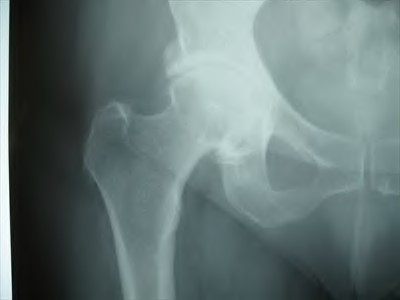

Figures A and B are pre-operative and intra-operative radiographs of a 67-year-old male that has undergone a left total hip arthroplasty under general anesthesia. The patient had no motor deficits preoperatively. During the operation, the trial acetabular and femoral components were positioned and reduced with no complication. Intraoperative leg lengths were equal. Before implanting the real components, the surgeon and anaesthesiologist performed a wake up test, which revealed that the patient was unable to dorsiflex the left foot. What would be the most appropriate next step in the management of this patient?

This patient has undergone a left THA with significant leg lengthening. The biggest concern is stretch to the sciatic nerve. The most appropriate step at this stage would be to perform a subtrochanteric osteotomy to decrease leg length and sciatic nerve stretch.

Patients with DDH that have undergone a large limb-lengthening procedure are at a greater risk due to the significant stretch of the sciatic nerve. Intraoperative procedures that have been shown to prevent this outcome include good pre-operative planning, limb lengthening